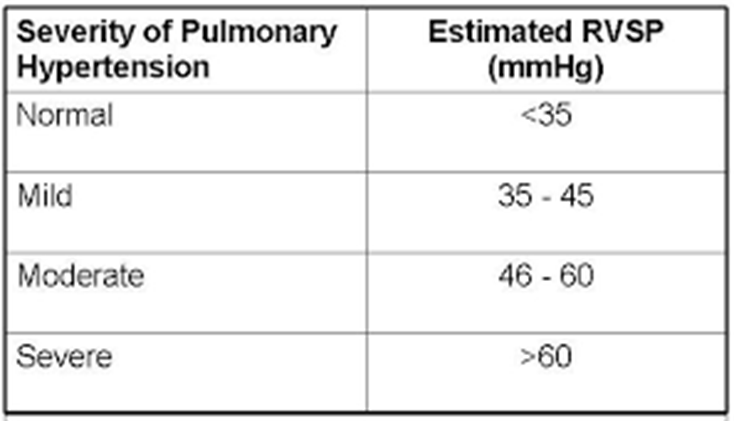

Right Ventricular Systolic Pressure (RVSP) is used to

RVSP is used to estimate right side pressures in the vessels leading to the lungs. This is used to determine pulmonary hypertension.

TR Vmax + RAP= RVSP

Pulmonary Hypertension (PHTN)

PAP elevation

caused by another disease

not a disease of pulmonary vessels

identified by:

elevated SPAP

elevated PVR (The resistance the RV must overcome

Pulmonary Atrial Hypertension (PAH)

Chronic, an incurable subgroup of PH

PAP elevation

Caused by pulmonary vessel disease

Identified by:

elevated SPAP (> 25 mmHg at rest or > 30 mmHg with exercise)

RVSP / Systolic pulmonary artery pressure (SPAP) determined by the TR

TR Max PG + RAP = RVSP/SPAP